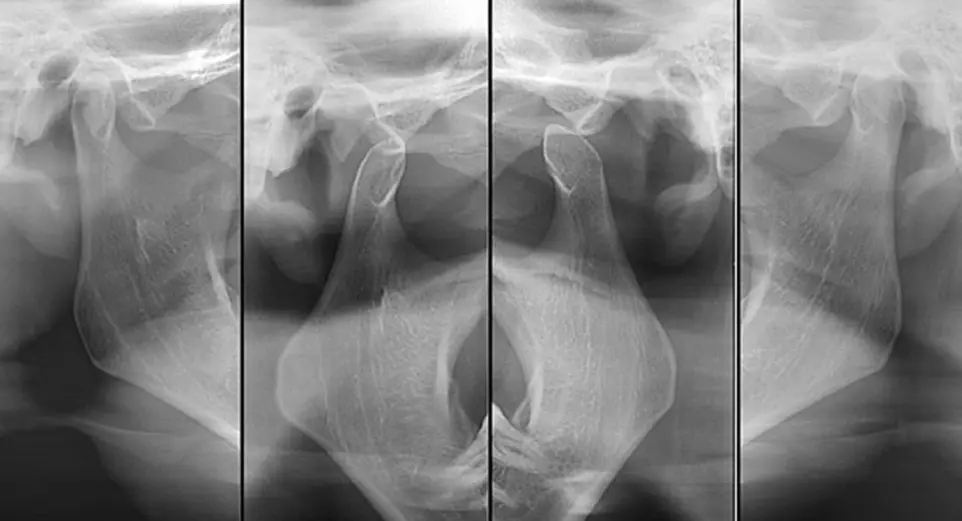

• Radiografía ATM: Para evaluar la Articulación Temporomandibular y detectar problemas de mandíbula.

Radiografía ATM

Boca Abierta / Boca cerrada

articulación temporomandibular